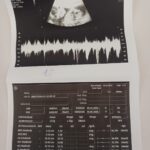

İrem Çağla ZİNCİRLİ-Fırat ALKIZ/İSTANBUL, – İSTANBUL’da, tüp bebek yöntemiyle hamile kalan 32 yaşındaki Nazire Aksoy Aydoğan, bayıldığı için hastaneye kaldırıldı. Yapılan muayenelerde, 5,5 aylık hamile olan Aydoğan’ın beyninin sağ tarafında 7 santimetre çapında bir tümör tespit edildi. Bu tümör, bebeğe zarar vermeyecek bir şekilde gerçekleştirilen ve 4 saat süren cerrahi operasyonla çıkarıldı. Ameliyat sonrası, hem anne hem de bebeğin sağlık durumlarının iyi olduğu bildirildi.

2020 yılında evlenen Nazire ve Ercan çifti, çocuk sahibi olabilmek için 6 yıldır süren tedavi sürecinin ardından tüp bebek yardımıyla bu mutlu haberi aldılar. Nazire Aydoğan, 5’inci ayına girdiği hamileliğinde bir sabah bayıldığını ve sara nöbeti geçirdiğini anladı. Hiç nöbet geçirmemiş olan genç anne, ambulansla hastaneye kaldırıldı. İlk müdahale sonrası net tanı alamayan ve evde ağrıları artan Aydoğan, başka bir hastaneye başvurdu. Çekilen tetkiklerde Aydoğan’ın beyninde 7 cm’lik bir tümörün olduğu belirlendi. Bebeği kaybetme riski oluşunca tedavi istemeyen Aydoğan’ın ameliyat süreci, beyin ve sinir cerrahisi, kadın hastalıkları ve doğum ile anestezi uzmanları tarafından titiz bir şekilde planlandı.

Hamileliğin getirdiği risklere rağmen, anne ve bebeğin sağlık durumları göz önüne alınarak ameliyat kararı alındı. Bebeğe zarar vermeyen anestezi teknikleri kullanılarak gerçekleştirilen operasyon 4 saat sürdü ve tümör tamamen çıkarıldı.

Herhangi bir nörolojik kaybın yaşanmadığı bildirilen hastada, ameliyat sonrası anne ve bebeğin sağlık durumlarının gayet iyi olduğu, bebeğin 23’üncü haftasında olduğu ve erkek olduğu öğrenildi.